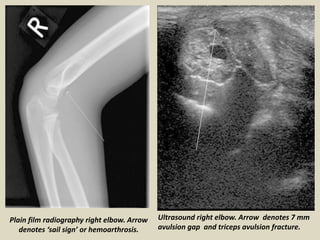

Ultrasound right elbow. Arrow denotes 7 mm

avulsion gap and triceps avulsion fracture.

Plain film radiography right elbow. Arrow

denotes ‘sail sign’ or hemoarthrosis.